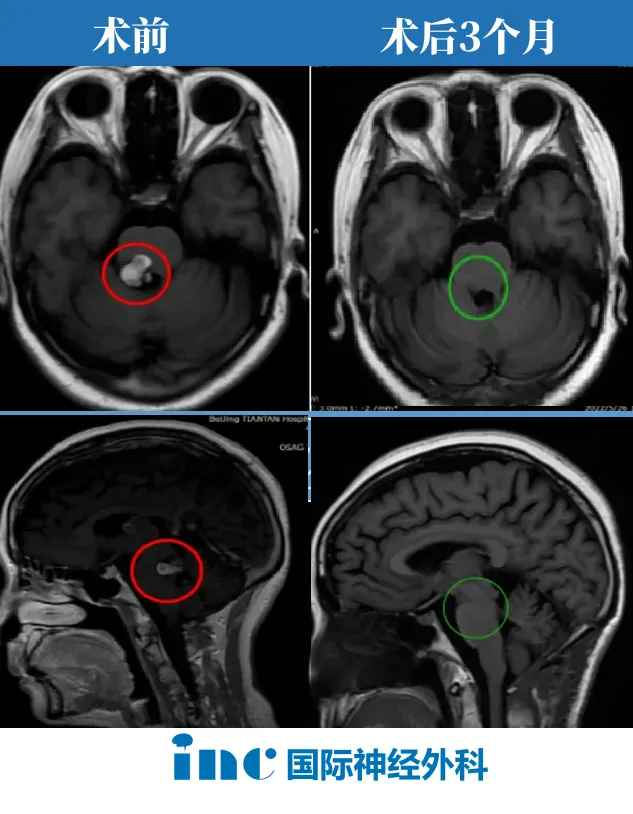

术后三个月,复查MRI的结果带来了期盼已久的好消息:病灶实现全切,无残留。虽然右腿功能仍需漫长的康复过程,但"随时可能再出血"的致命威胁终于解除。生活,重新有了安稳的盼头。